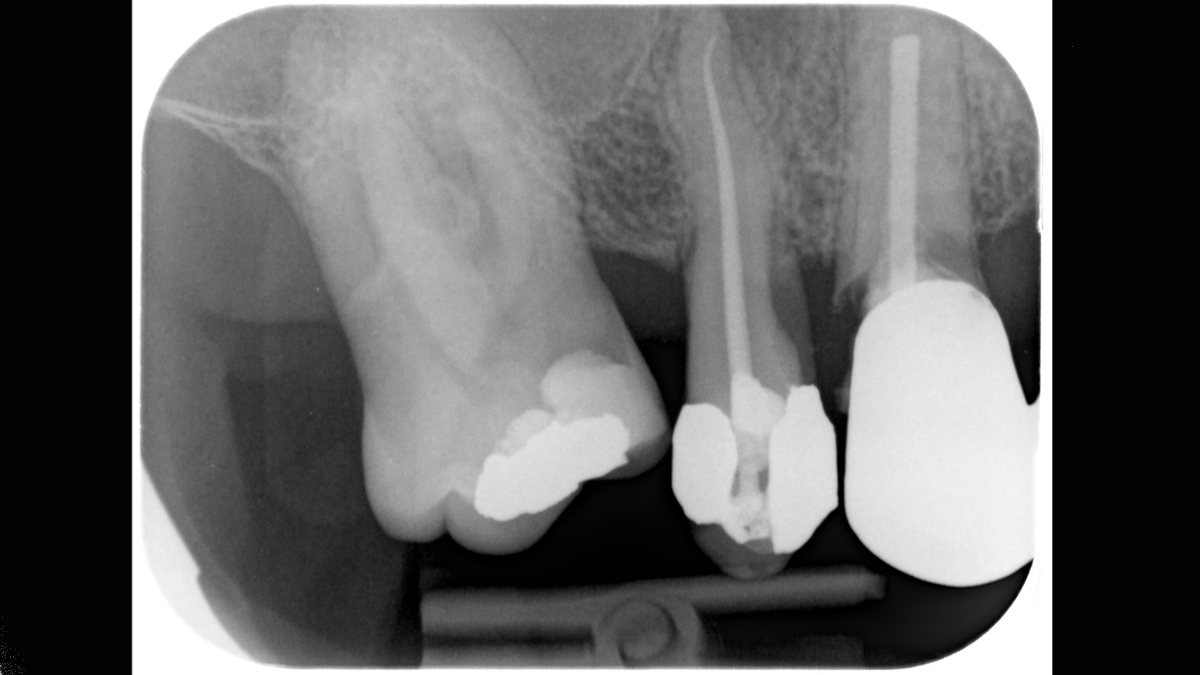

Xios Scan provides a gentle, easy introduction into the world of digital X-ray imaging. If you want to switch from film to digital without having to give up your tried-and-true working methods, imaging plate technology offers you a myriad of possibilities. You can experience many of the advantages of digital imaging without a darkroom and chemicals while your team continues its regular workflow.

The Xios Scan integrates seamlessly with the Dentsply Sirona X-ray units and software to deliver better, safer and faster intraoral diagnostics.